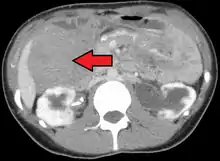

![]() | |

Desmoid tumor as seen on CT scan | |